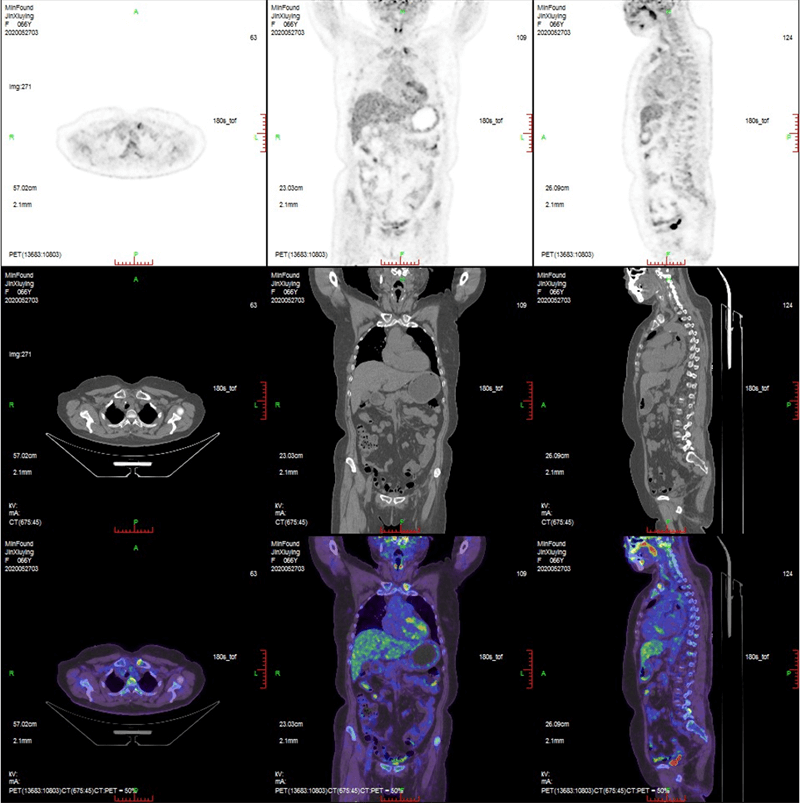

ScintCare PET/CT 720E

ScintCare PET/CT 720E uses the 4th-generation PET detector with which lutetium-yttrium oxyorthosilicate (LYSO) crystals are individually coupled to SiPM detectors without the optical conductor. This digital SiPM-based detector ensures 100% crystal coverage to the SiPM and greatly improves photons efficiency and images quality.

The 20.16 cm axial FOV compare to the conventional 16 cm axial FOV PET/CT, it speeds up the scanning process allowing greater patient throughput.

Respiratory gated PET/CTaims to eliminate the effects of motion artefact and provide a more accurate interpretation of pulmonary nodules and lymphadenopathy.

MinFound's digital gating technology is implemented directly, and can be set in the exam application. This technology not only saves additional preparation time, but also reduces overall examination duration.